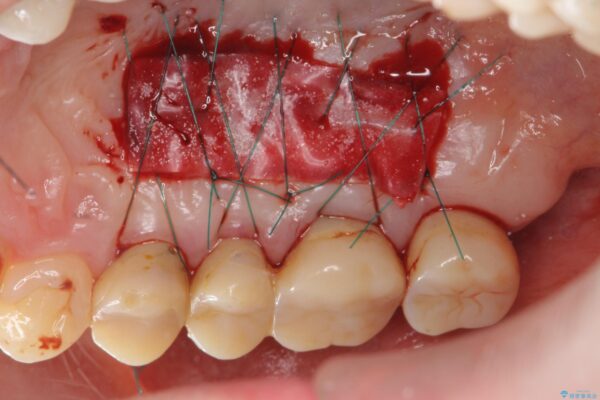

また、機能後のインプラント周囲の清掃性を高めるため遊離歯肉移植術を行っています。

インプラント周囲に強固な歯ぐきを移植することで、歯ブラシがしやすくなりインプラント周囲炎対策となります。

治療中

遊離歯肉移植術を伴うインプラント治療 治療中画像 遊離歯肉移植術を伴うインプラント治療 治療中画像 遊離歯肉移植術を伴うインプラント治療 治療中画像 遊離歯肉移植術を伴うインプラント治療 治療中画像 遊離歯肉移植術を伴うインプラント治療 治療中画像 遊離歯肉移植術を伴うインプラント治療 治療中画像